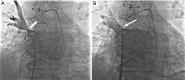

Acquired pulmonary vein stenosis (PVS) is an uncommon occurrence in adults, but one that carries significant morbidity/mortality. PVS can be secondary to neoplastic infiltration/extrinsic compression, non-neoplastic infiltration/extrinsic compression, or iatrogenic intervention. This article: (I) reviews the common causes of acquired PVS; (II) illustrates direct and indirect cross-sectional imaging findings in acquired PVS (in order to avoid misinterpretation of these imaging findings); and (III) details the role of imaging before and after the treatment of acquired PVS.